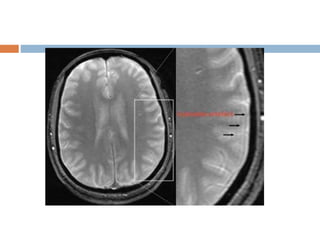

Gibbs or truncation artifact

 Commonly seen at the low signal intensity spinal

cord with high signal intensity CSF on T2WI of the

spine.

 As the signal is sampled, some data is necessarily

omitted in k-space, causing the signal intensity of

a given pixel to vary from its ideal signal intensity.

 Appearance

 Bright and dark lines.

 Solution

 Increase matrix size.

Gibbs or truncationartifact  Occurs at high contrast boundaries.  Due to truncation(omission) of sampled signals.  Commonly seen at the low signal intensity spinal cord with high signal intensity CSF on T2WI of the spine.  As the signal is sampled, some data is necessarily omitted in k-space, causing the signal intensity of a given pixel to vary from its ideal signal intensity.  Appearance  Bright and dark lines.  Solution  Increase matrix size.